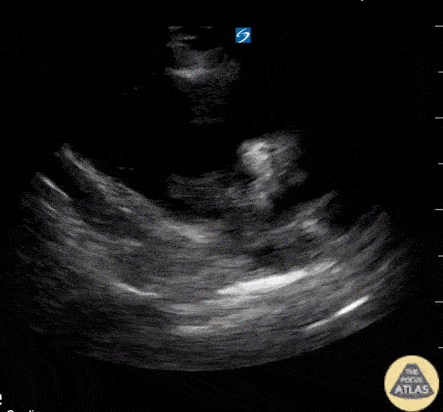

Right Ventricular Dysfunction - Hyperechoic lesion with enlarged RV from PE

[SonoClipShare Submission]: PLA demonstrating a small LV, an enlarged RV, and a hyperechoic lesion moving back and forth (later views confirming moving between RA and RV). 1st of 4 views to be submitted on the same case. This was an unfortunate 40ish y/o 6 months s/p CVA 2/2 ruptured aneurysm and IDDM presenting with 4 days of "feeling weak". Found to have a HR of 120 to 130, a BP around 90-100/60-70 and pulse ox of 90 - 92%. POCUS lungs were normal. Started on heparin, CTA confirmed PE and went to IR for catheter-directed tPA lysis with normalization of BP, HR and good clinical outcome. Image courtesy of John Hipskind MD